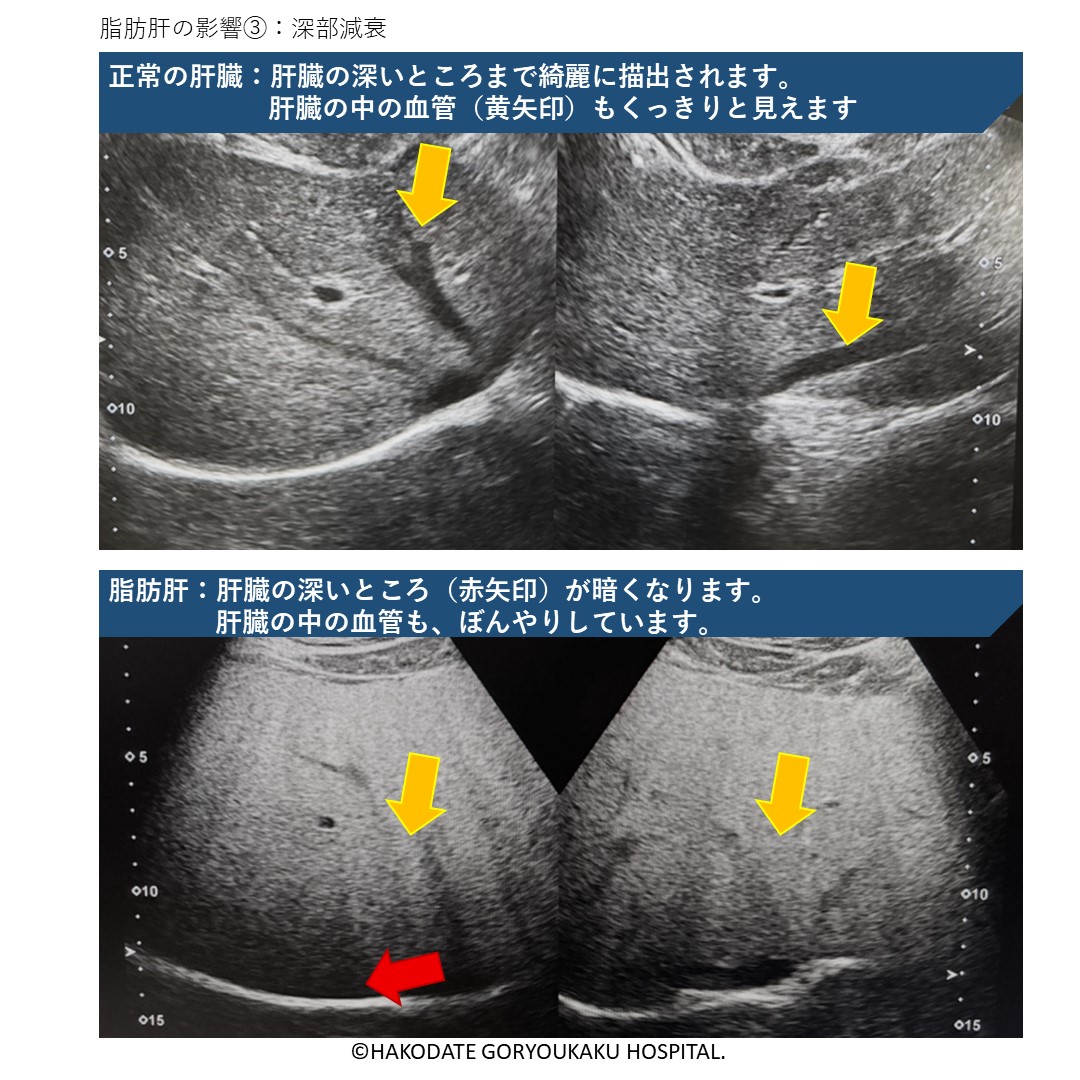

深部減衰

正常の肝臓であれば超音波は深い所まで届き、肝臓は下まで綺麗に描出されます。脂肪肝では脂肪により超音波が分散され、深い所に届かず、暗く見えにくくなります。